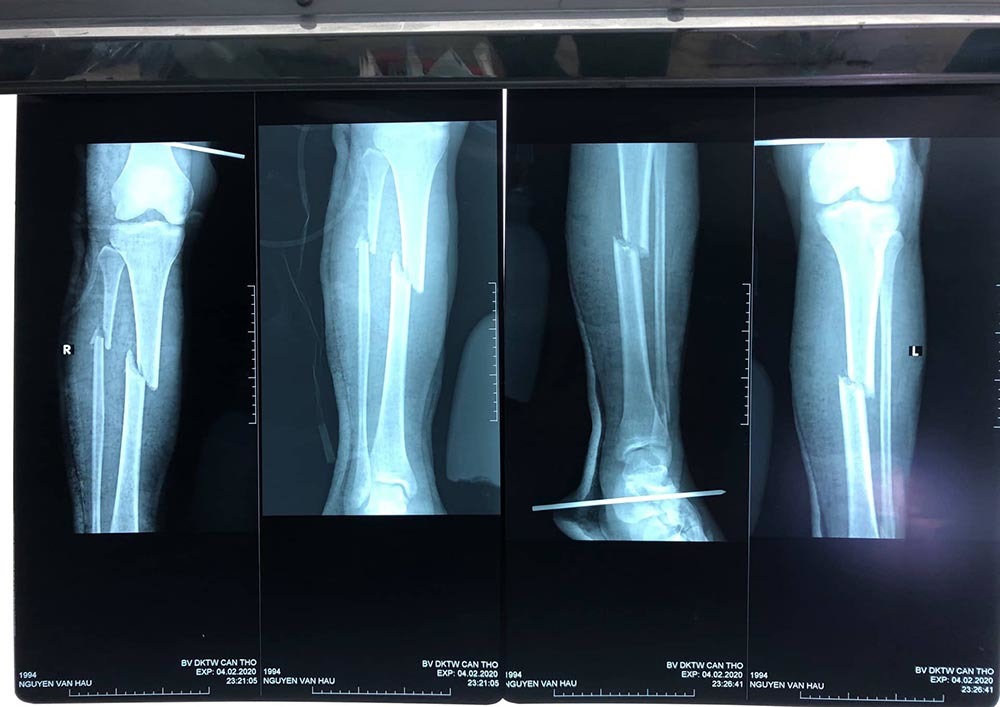

| Hình ảnh gãy nhiều xương ở 6 vị trí khác nhau của bệnh nhân |

Qua hội chẩn, bác sĩ xác định bệnh nhân bị đa tổn thương, gãy hở mỏm khuỷu trái, gãy hở xương đùi, bàn chân trái, gãy kín 2 xương cẳng chân trái, gãy kín xương đùi phải và gãy kín 2 xương cẳng chân phải. Bệnh nhân có chỉ định phẫu thuật. Bệnh nhân được thực hiện 2 lần phẫu thuật.